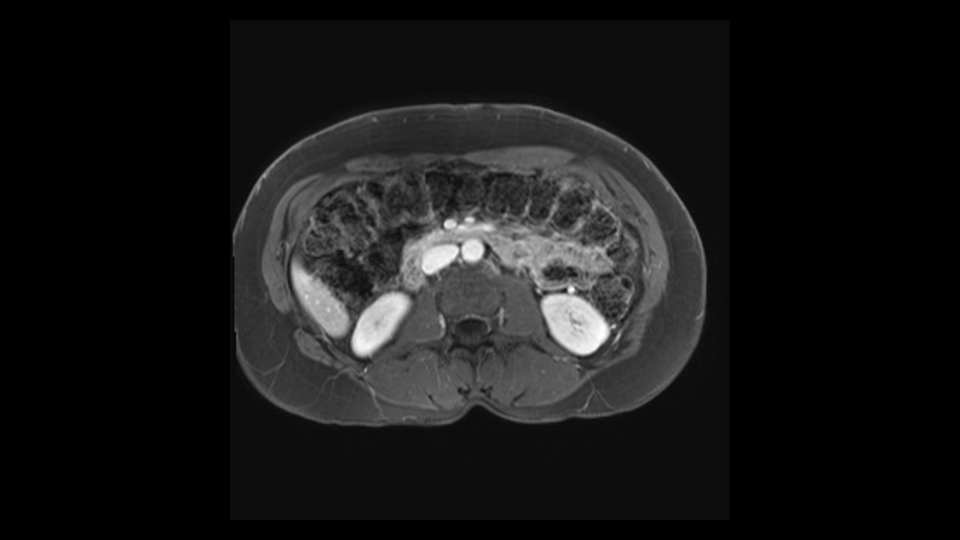

The slowing down moments or considerations that I give when I look at the scan and plan my distal pancreatectomy is how far away the tumor is to the portal vein and do I have to formally create a tunnel behind the pancreas on top of the portal vein or do I have to take the pancreas further to the left of the portal vein or the patient’s left of the portal vein. So here I can see that here is the tumor here. I can see that the tumor is a fair way away to the patient’s right and so I will likely not have to take or create the tunnel formally in this procedure. And that speaks a lot to the resection margins. So its important when you’re doing a distal pancreatectomy or any procedure potentially for oncologic reasons to get clearance of the tumor and to take the tumor kind of intact.

I mentioned earlier that transection at the neck is the area that I would normally do as long as I have good margin from the lesion. And if the margin is not enough, I would go further to go to the right of the PV-SMV area at the junction and do the transection at that point.

Once the jaws have completely been opposed, then I would fire the staple and perhaps leave another few seconds before I unlock and release the staple so that would ensure opposing the pancreatic duct. Since this is a spleen preservation, we go from the medial to the lateral to try to remove as much of the tail as possible. We don’t want to leave the tail there at the hilum of the spleen. So again this is another slow down moment because the splenic vessels at the hilar area can still be injured while doing the dissection. So dissection just continues to remove the entire pancreas until the tail. This would complete the procedure.